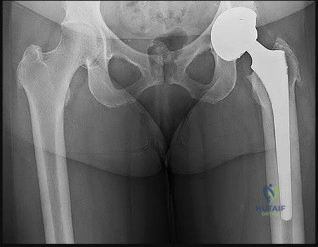

Question 56

In a healthy adult, the predominant blood supply to the weight-bearing dome of the femoral head is provided by the lateral epiphyseal artery. This vessel is a terminal branch of which of the following?

In the developing child prior to physeal closure, the primary blood supply to the capital femoral epiphysis is derived from the lateral epiphyseal artery. This vessel is a terminal branch of which artery?

Explanation